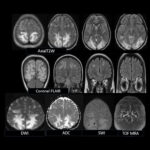

Neurosurgery and neuroradiology always go hand in hand. This little weekly activity is going to enhance the scan reading skills of our audience in an interactive way. Waiting for the answer for a week will keep the curiosity alive and will keep our target audience hooked to the website. It will prove to be a seamless share of knowledge and reading skills.

Dr. Saqib Kamran Bakhshi started the PANS Weekly Image Challenge in 2022, and his creativity and efforts made it a popular activity; engaging trainees and consultants in Pakistan and abroad.